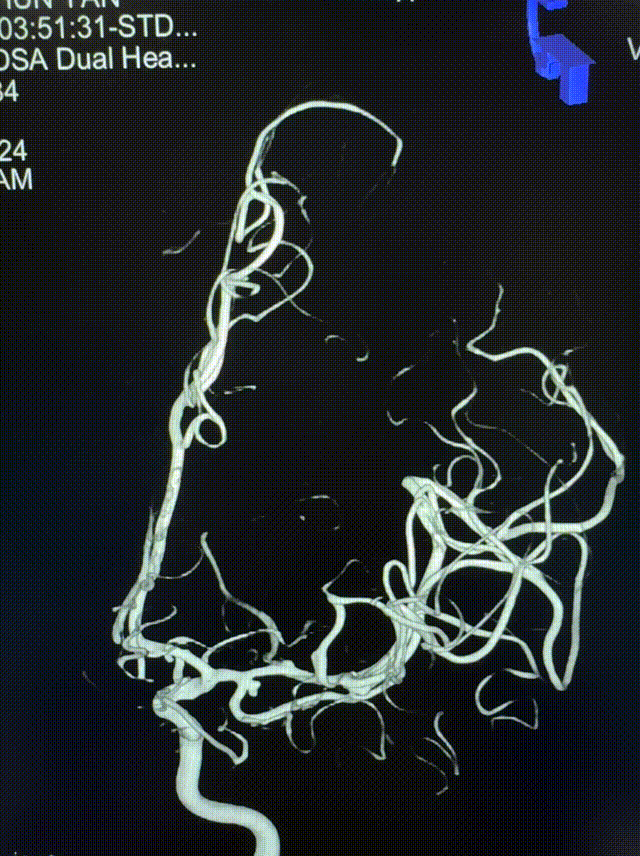

急诊头颅CTA:左侧大脑中动脉M1远端分叉处动脉瘤,左侧大脑中动脉M1段颞干分叉处动脉瘤。

左侧大脑中动脉M1段颞干分叉处动脉瘤

左侧大脑中动脉M1远端分叉处动脉瘤